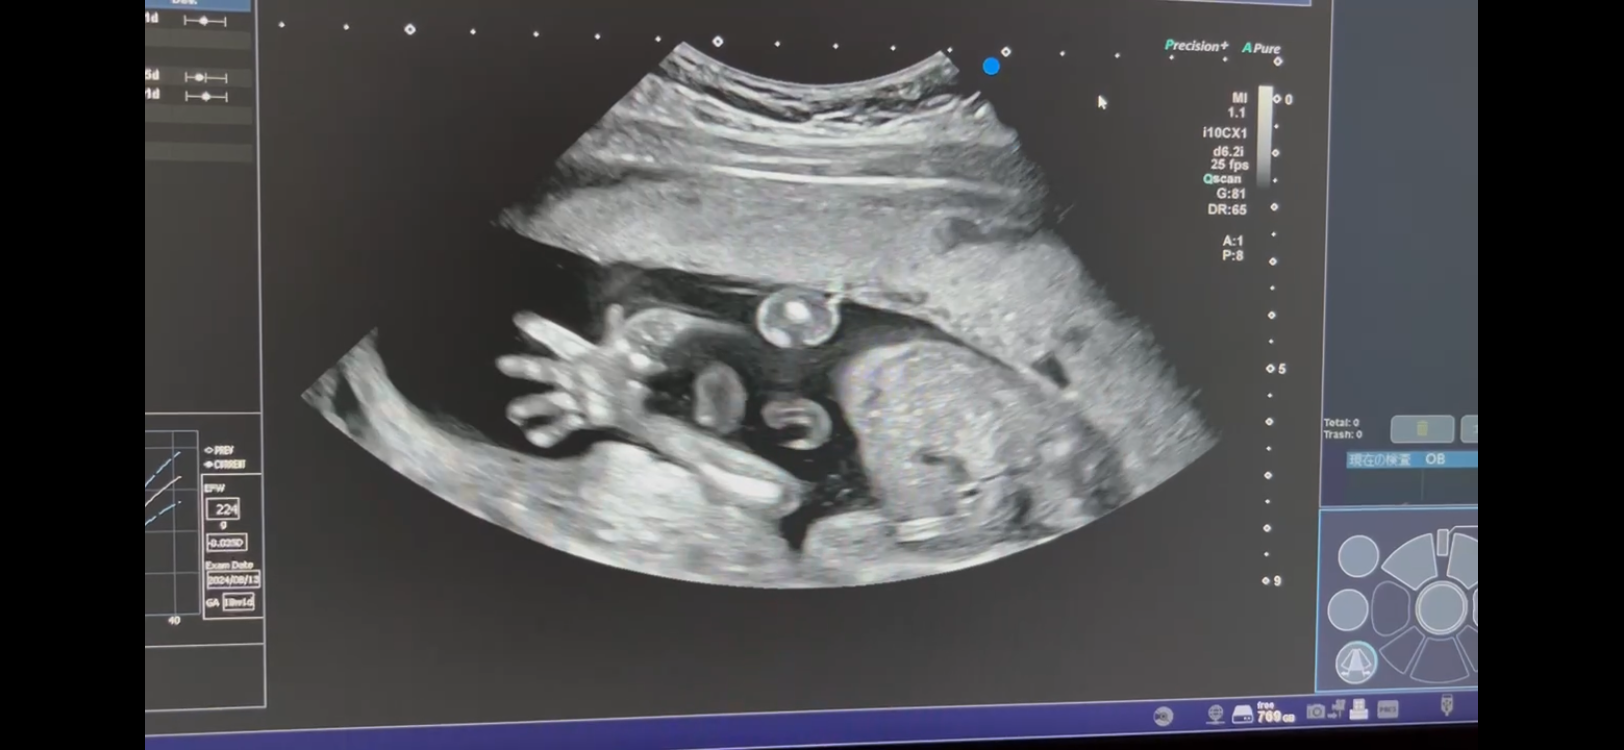

30週の今、胎児の状態だと異常な所見は全くなく順調。初期の不安も吹っ飛ばしてくれるぐらいぐぱちゃんはお腹の中でムニョムニョ元気!

あ、「ぐぱちゃん」は12週ごろからエコーで手をグーパーわしわししてたので旦那が命名。